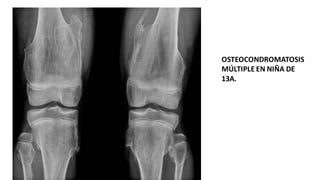

OSTEOCONDROMATOSIS

MÚLTIPLE EN NIÑA DE

13A.